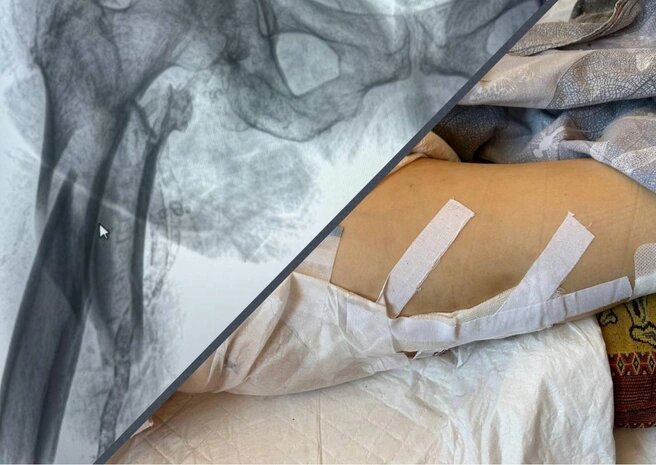

Пенсионерка получила тяжелую травму и скончалась через неделю в больницеИсточник:предоставлено семьей погибшей

Диагноз, поставленный в самарской ГБ № 10: «Оскольчатый перелом диафиза бедренной кости». Внучка пенсионерки Евгения в разговоре с корреспондентом 63.RU уточнила, что травма оказалась чрезвычайно тяжелой.

«Кость была раздроблена как вилка и торчала в артерию. Врачи почти двое суток не решались на операцию, боялись, что она не перенесет. Как нам объясняли, бабушка могла скончаться прямо на операционном столе», — рассказывает Евгения.